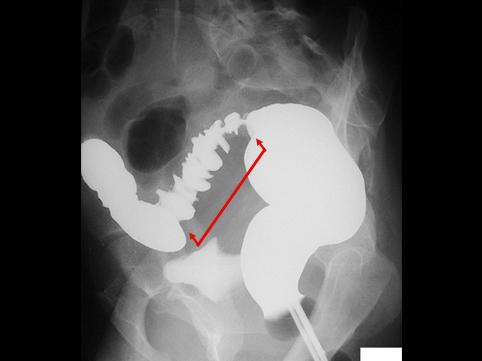

Caso de Endometriosis del Sigmoides que acompaña evidente estenosis

Lesión que asemeja tumoración/Endometriosis

colon/sigmoides

Rayos X

40 -